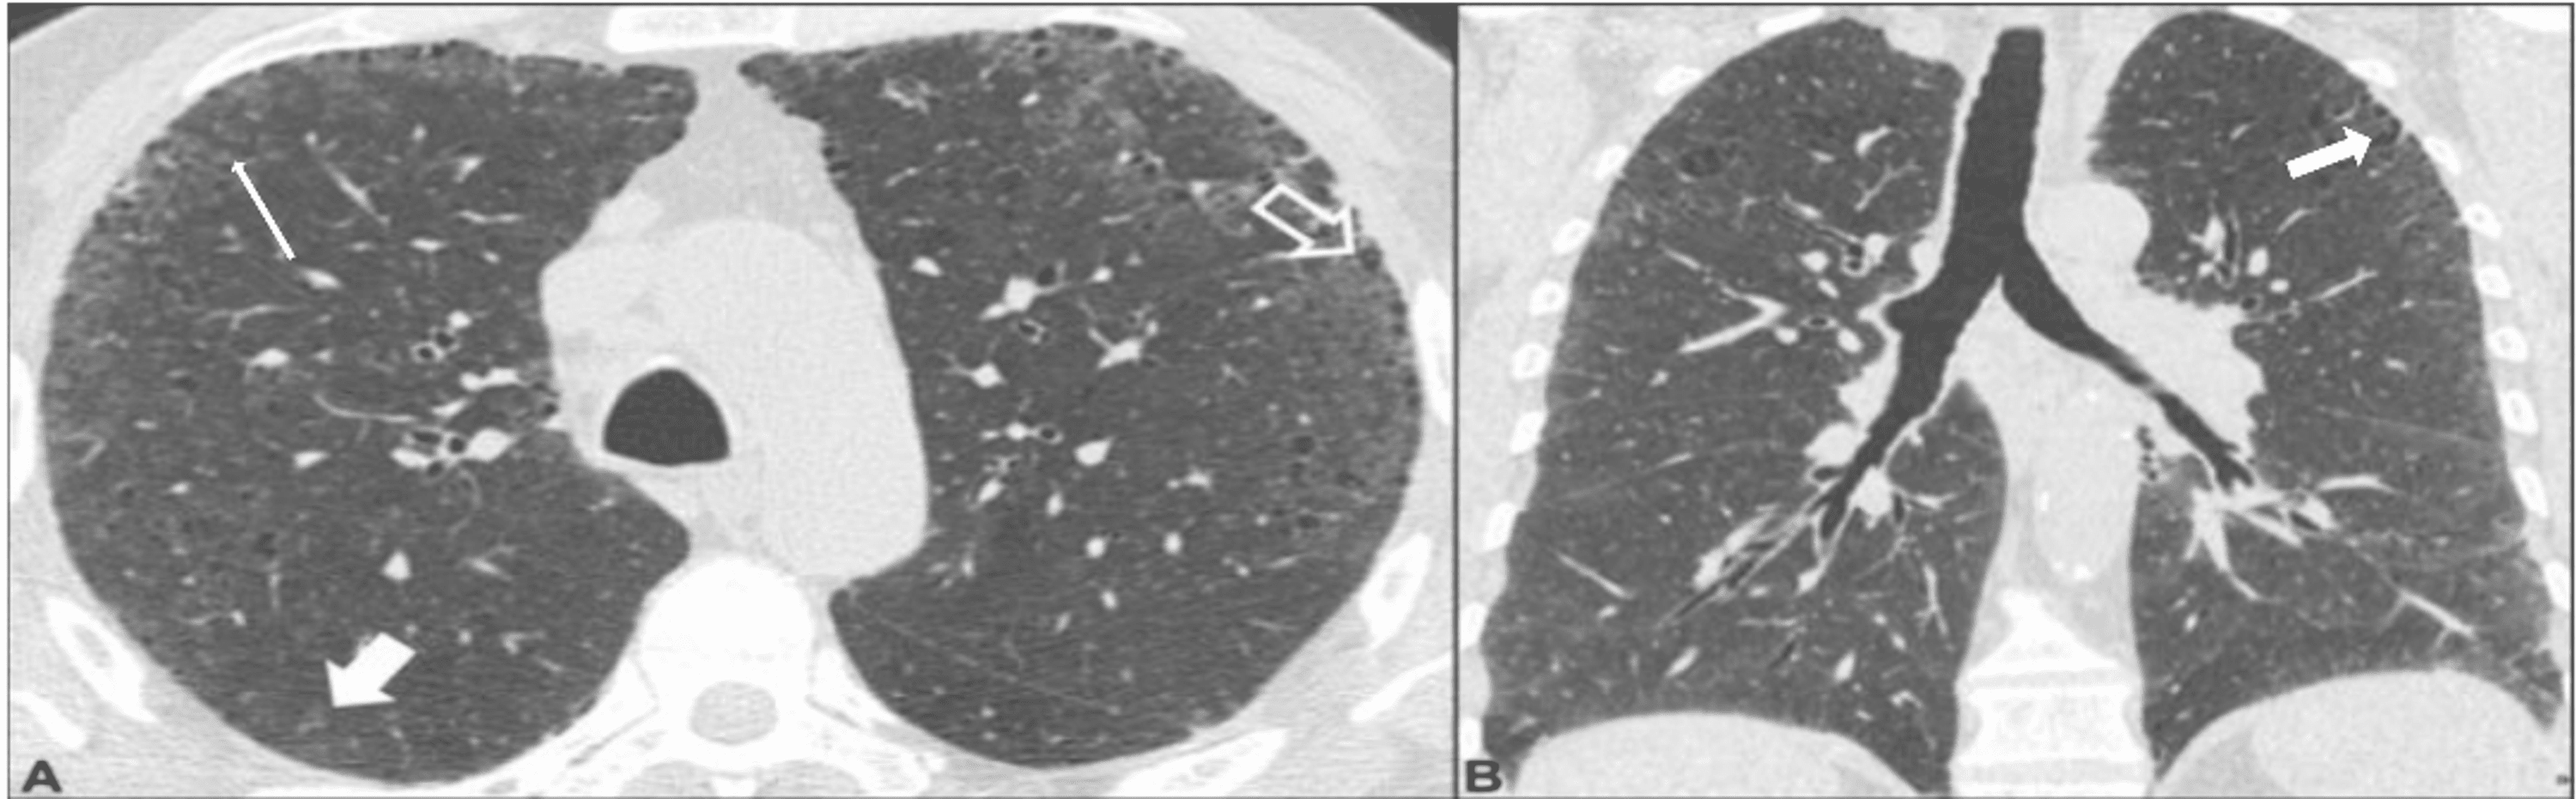

Challenges in pulmonary fibrosis · 1 Use of high resolution CT Smoking Associated Interstitial Lung Disease cigarette smoking is a recognized risk factor for development of interstitial lung disease (ild). Cigarette smoking is associated with a variety of pathologic conditions that affect the airways and. available evidence suggests most cases of desquamative. cigarette smoking is a risk factor for interstitial lung abnormalities (ilas) and interstitial lung diseases (ilds). smoking is also a. Smoking Associated Interstitial Lung Disease.

Changes in HRCT findings in patients with respiratory bronchiolitis Smoking Associated Interstitial Lung Disease available evidence suggests most cases of desquamative. cigarette smoking is a risk factor for interstitial lung abnormalities (ilas) and interstitial lung diseases (ilds). Cigarette smoking is associated with a variety of pathologic conditions that affect the airways and. smoking is also a risk factor for combined pulmonary fibrosis and. cigarette smoking is a recognized risk factor. Smoking Associated Interstitial Lung Disease.

Changes in HRCT findings in patients with respiratory bronchiolitis Smoking Associated Interstitial Lung Disease cigarette smoking is a recognized risk factor for development of interstitial lung disease (ild). cigarette smoking is a risk factor for interstitial lung abnormalities (ilas) and interstitial lung diseases (ilds). Cigarette smoking is associated with a variety of pathologic conditions that affect the airways and. smoking is also a risk factor for combined pulmonary fibrosis and. . Smoking Associated Interstitial Lung Disease.

Features of nonfi brotic smokingrelated interstitial lung disease Smoking Associated Interstitial Lung Disease cigarette smoking is a recognized risk factor for development of interstitial lung disease (ild). smoking is also a risk factor for combined pulmonary fibrosis and. cigarette smoking is a risk factor for interstitial lung abnormalities (ilas) and interstitial lung diseases (ilds). Cigarette smoking is associated with a variety of pathologic conditions that affect the airways and. . Smoking Associated Interstitial Lung Disease.